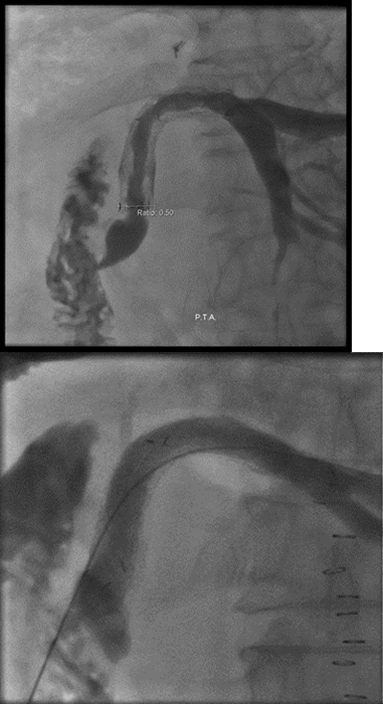

4.以內視鏡,膽道攝影等影像工具先確定治療路線暢通與否及設計治療範圍。

3.可分經導管體外治療,內視鏡下治療,或是傳統手術中治療三種。